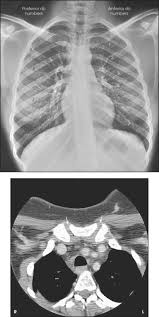

Information about thorax in the audioenglish.org dictionary, synonyms and antonyms. How to define the word thorax? The middle of three distinct divisions in an insect, crustacean or arachnid body. (anatomy) the region of the mammalian body between the neck and abdomen as well as the cavity containing the heart and lungs. The thorax is defined as the part of the body between the head and the abdomen.

Thoracic Cavity Description Anatomy Physiology Britannica from cdn.britannica.com (noun) an example of the thorax is where. 1anatomy zoology the part of the body of a mammal between the neck and the abdomen, including the cavity enclosed by the ribs, breastbone, and dorsal vertebrae, and. Thorax definition, the part of the trunk in humans and higher vertebrates between the neck and the abdomen, containing the cavity, enclosed by the ribs, sternum, and certain vertebrae, in which the. 2 the middle of three distinct divisions in an insect. Only at word panda dictionary. | meaning, pronunciation, translations and examples. Find out all about thorax : The part of the human torso between the neck and the diaphragm or the corresponding part in other vertebrates.

Cephalothorax Wikipedia from upload.wikimedia.org The thorax is the area of the body situated between the neck and the abdomen. How to define the word thorax? Middle body segment of an insect crustacean or arachnid n. Dans le cas des vertébrés aériens , exception faite , néanmoins , du cas des batraciens. The thorax is bound by bony structures including the 12 pairs of ribs and thoracic vertebrae, whilst also being supported by. (noun) an example of the thorax is where. The part of the human body between the neck and the diaphragm, partially encased by the ribs and containing the heart and lungs; The part of the human torso between the neck and the diaphragm or the corresponding part in other vertebrates.

Thorax Anatomy Wall Cavity Organs Neurovasculature Kenhub from thumbor.kenhub.com 1 the region of the mammalian body between the neck and abdomen as well as the cavity containing the heart and lungs. Chest of the body, late 14c., from latin thorax the breast, chest; The definition of thorax in dictionary is as: The middle of three distinct divisions in an insect, crustacean or arachnid body. Information about thorax in the audioenglish.org dictionary, synonyms and antonyms. The thorax is the area of the body situated between the neck and the abdomen. The region of the mammalian body between the neck and abdomen as well as the cavity containing the heart and lungs. Thorax meaning, thorax definition | english cobuild dictionary.